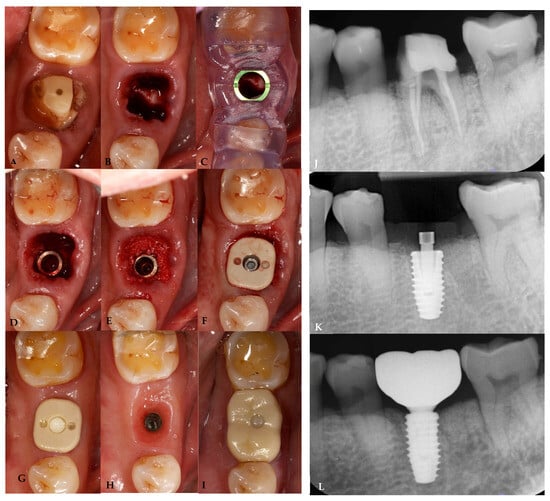

2.7. Case Presentation